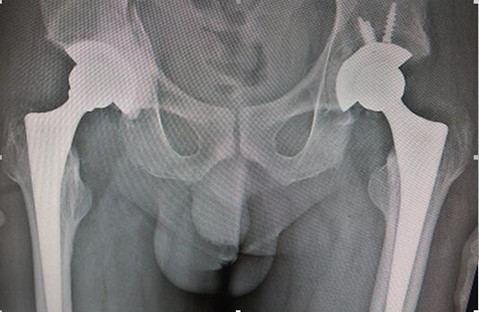

强直性脊柱炎、双侧股骨头坏死、

双侧髋关节融合患者的双侧全髋关节置换术

刘先生29岁,于十余年前无明显诱因出现浑身乏力、消瘦、背部肌肉僵硬,晨起明显,活动后缓解的症状,随着病情逐渐发展,出现腰骶部坚硬感,间歇性出现腰痛和两侧臀部疼痛,放射至大腿,经多方诊治,最终确诊为强直性脊柱炎。由于刘先生的病情迁延不愈,双侧髋关节疼痛愈发严重,于是前往当地医院检查治疗,诊断为双侧股骨头无菌性坏死,自行保守治疗。6年前逐渐出现双侧髋部旋转及屈伸活动障碍,严重影响日常生活。3年前开始出现颈部僵硬,活动受限,保守治疗多次均未好转。为求进一步诊治,刘先生及其家人来到了骨外一科。经过仔细查体及辅助检查,刘先生被诊断为:强直性脊柱炎、双侧股骨头坏死、双侧髋关节融合。白玉江主任建议其做:双侧全髋关节置换。经过3个小时的手术,刘先生的双侧全髋关节置换手术顺利完成,目前,刘先生恢复良好。

手术难度:因患者双髋关节融合,无活动度,大大增加手术操作难度,又因肺功能略差,全麻插管难度大大提高,麻醉科张宏伟主任行纤维气管镜清醒插管,手术顺利。

术前X线

术后X线